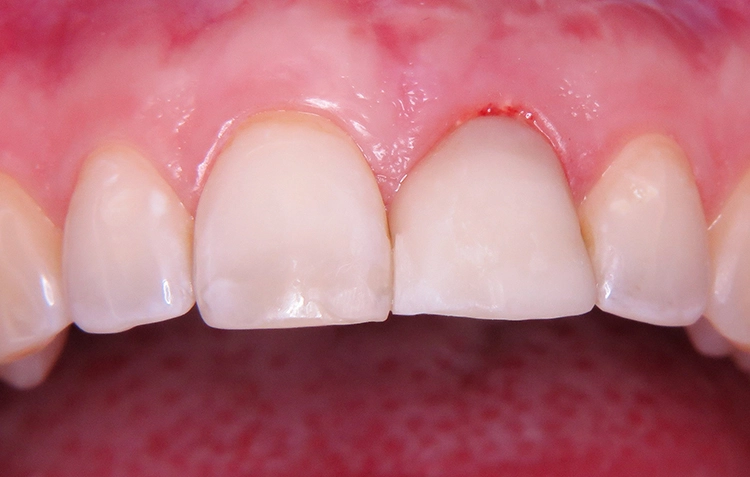

Fertigstellung und Einsetzen der temporären Implantatkrone

Die gedruckte Implantatkrone kann auf Wunsch mit lichthärtenden Laborkompositen oder Malfarben charakterisiert werden. Im vorliegenden Fall erfolgte lediglich eine Politur der temporären Krone (Abb. 21). Basierend auf dem Variobase® Aufbau (Straumann) konnte die Krone 20 Stunden nach der Insertion des Implantates regio 21 im Patientenmund verschraubt werden (Abb. 22 bis 25). Funktionell wurde die Restauration statisch sowie dynamisch außer Okklusion gestellt. Die Patientin fühlte sich mit dem erzielten Ergebnis wohl. Im komplett digitalen Workflow und innerhalb einer nur kurzen Zeit konnte sie mit einem adäquaten, provisorischen Zahnersatz aus der Praxis entlassen werden.

Theoretisch wäre die digitale Datenerfassung mit dem Intraoralscanner möglich, allerdings sind die Scanpfosten nicht radioopak, so dass eine exakte radiologische Kontrolle nicht möglich ist. Im Dentallabor wurde zunächst das vollkeramische Abutment gefertigt und nach dessen Einprobe die vollkeramische Krone hergestellt (Abb. 28 bis 30). Nach dem Verschrauben der Krone im Mund konnte der Schraubenkanal mit Komposit verschlossen werden. Es zeigt sich eine stabile Situation mit einem gesunden peri implantären Weichgewebe und harmonischem Gingivaverlauf (Abb. 31a und b).